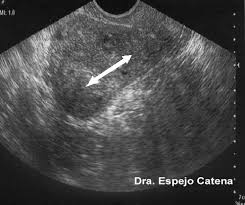

-       Imagen: eco vaginal / abdominal. RMN

Eco abdominal o vaginal: permiten ver el número y tamaño de miomas. En principio se hace preferentemente vaginal. Se hará abdominal cuando el tamaño y localización del mioma lo indiquen.

RMN: no es una exploración muy frecuente para los miomas. Tiene mayor precisión que la ecografía vaginal para definir la localización del tumor (70 % precisión) y se utiliza para cuando existan dudas sobre la benignidad o la malignidad de la tumoración, es decir  sirve e para diferenciar el mioma del sarcoma y del mioma celular (un tumor entre la benignidad  y la malignidad que será explicado posteriormente).